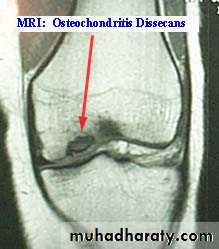

2.MRI

.Meniscal & ligamentous tears in the knee .

Osteochondritis :